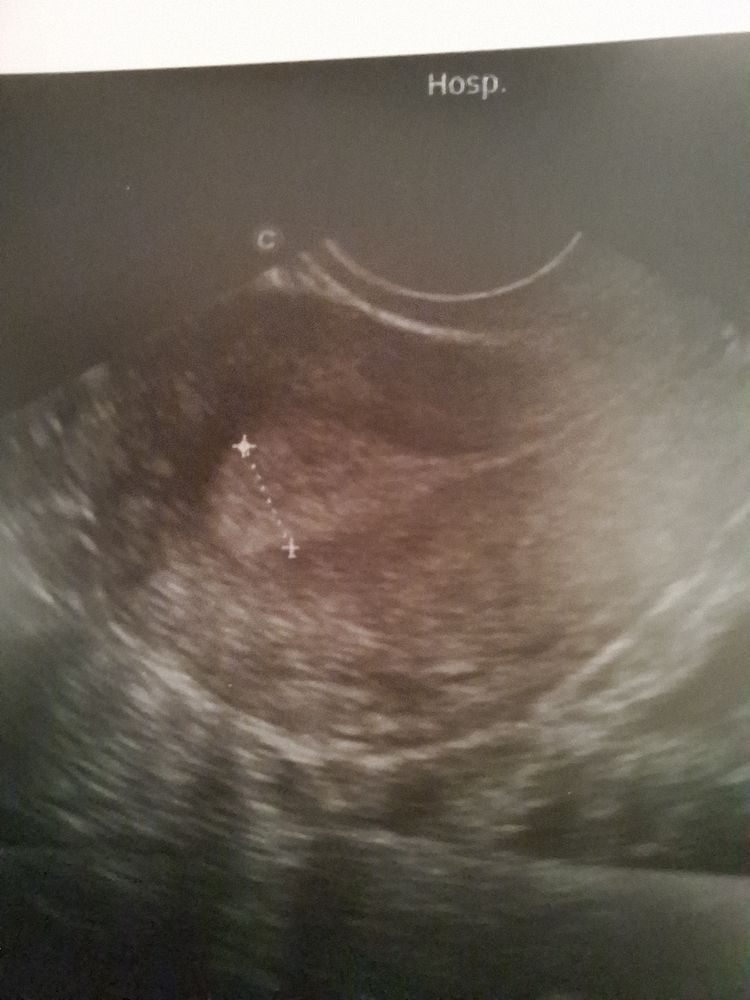

Аня, вот это как я понимаю эндометрий или нет? Изображение

Светлана , вот у вас эндометрий, слева это ближе ко дну матки, а справа к шейке Изображение